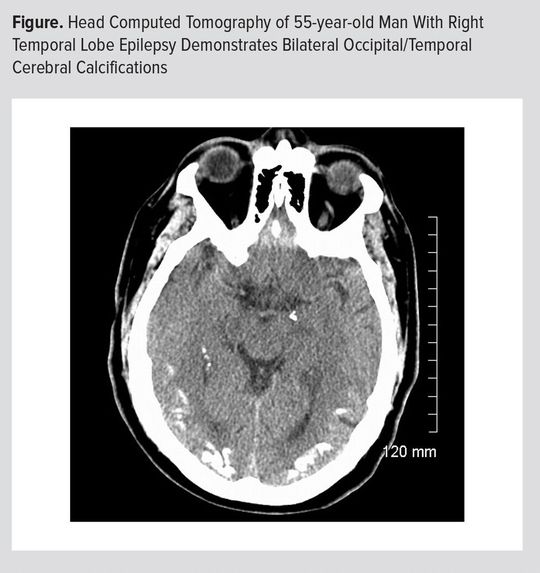

This is a case report of a 55-year-old man with medication refractory right temporal lobe epilepsy since adolescence. He was found to have bilateral posterior cerebral calcifications on routine head computed tomography with confirmation on magnetic resonance imaging. He also had elevated antibody markers for celiac disease. He was diagnosed with the rare, but well-described syndrome of celiac disease, epilepsy, and cerebral calcifications (CEC). He failed a brief trial of gluten-free diet and went on to have a right temporal lobectomy with sustained freedom from disabling seizures. This case is an example of the growing recognition of neurologic disorders associated with celiac disease. It also provides an example of the characteristic radiographic sign associated with CEC.